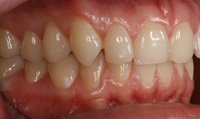

Lingual Veneers - Why? To restore worn-away enamel from acid erosion due to eating disorders.Lingual veneers are veneers that are placed on the inside, or lingual, surface of the front teeth. Rather than remove any healthy enamel from the remaining front and back sides of the teeth to do crowns, lingual veneers offer a conservative alternative for those who have experienced acid erosion, or tooth wear, of the lingual surfaces due to the detrimental effects of eating disorders such as bulimia. The goal is to build up and restore worn away teeth while preserving as much of the natural, beautiful and healthy tooth structure as possible. This strengthens and reinforces the tooth from further damage and drastically reduces sensitivity so a healthy diet and lifestyle can be resumed. Professional dental help for bulimia It is important to seek dental care if you have bulimia and to openly share with the dentist what is happening. Many dentists are caring professional people who understand the problems with bulimia and want to help. Without the dentist's help, the dental consequences of your bulimia can be severe. Dr. Berland can usually provide all of the dental services needed to restore the bulimic patient back to good dental health in a confidential and private manner. Additionally, Dr. Berland can help a bulimic patient manage the condition so that, even if they are continuing to have problems, the dental consequences of bulimia are lessened or eliminated. The Dallas Dental Arts services can be specially arranged for a bulimic patient so that all needed dental treatment can be intensively completed in a short period of time. This makes it possible for patients from out of town to complete their desperately needed dental care confidentially and in as few visits as possible. The Dallas Dental Arts can also assist in obtaining the funds for this care so everything that needs to be done can be completed. For more information on financial assistance, please click here. Dr. Berland has successfully cared for many patients suffering from bulimia and would be pleased to meet with you in a confidential consultation. Here, You can privately discuss your choices in dealing with your bulimia. Dr. Berland understands that you are struggling with bulimia and that it may take time to deal with the consequences of your bulimia. Privately speaking with Dr. Berland can be your first step in conquering your bulimia. Please consider calling (214)999-0110 and scheduling a consultation. You do not have to say why you are visiting, just that you would like a private consultation. If calling for an appointment is too embarrassing, you can first email Dr. Berland at drberland@dallasdentalspa.com or you can schedule a consultation and privately email him to let Dr. Berland know that you wish to talk about your bulimia. This young lady came to our office looking for a way to improve her smile, self-image and most importantly, her health. As a recovering bulimic patient, she had endured years of damage to her enamel from her previous history of eating disorders. In her case, the erosion wore all the way through her enamel and even into the soft, sensitive inner tooth layer, the dentin. She sought us out to find a way to restore her smile without further compromising the fragile condition of her teeth. Other dentists discussed filing her already thinned down teeth further and "strengthening" them with porcelain crowns. Our approach was completely different. Why take away more when you don’t have much to begin with? We recommended she try lingual resin veneers (on the backside of her teeth) followed by cosmetic one-stop bonding on the front and especially the edges of her teeth. This is a completely noninvasive and a purely additive procedure. She would be adding strength to her teeth, fortifying them rather than removing any of her remaining enamel, thereby reinforcing her teeth, improving her dental condition and creating the beautiful, yet natural, smile she desired. When the patient heard of this conservative treatment alternative, it made sense to her to preserve her teeth to maintain her health and restore her smile. Not only were the back sides of her teeth built out, length was added to replace what was worn over the years for a more youthful smile. After the no-shots, no-drilling, and no-pain appointment, her teeth were no longer sensitive to sweets, hot or cold. The patient was very pleased with her results. She not only gained a beautiful, new smile, but she also had a renewed confidence in herself and a reassurance of a healthier smile – and that means a healthier lifestyle as well! With all the focus of the media on diets, exercise equipment and personal care products, people are more concerned with their appearance and physical health than ever. In an effort to meet today's standard of beauty and "health", many people are quick to try the newest crash diet fad without ever realizing that this may, in fact, be the incorrect way to diet. These crash dieters who excessively fast, or try every new trend, tend to have a lack of, or decrease in certain vitamins, most notably Vitamins D, B-12 and calcium. They also tend to lack certain minerals and proteins in their diets. These are very important vitamins especially for the health of the teeth and gums. What can occur is that dieters tend to have a diet high in fruits which may contain a high content of natural sugars. These sugars tend to decay and erode the enamel of the teeth. Mints, used to combat the bad breath associated from Ketosis caused by an unbalanced protein diet and "so-called" Power Bars can further decay the teeth. Dieters also tend to take diet pills that may cause a decrease in saliva flow as a side effect. This decrease in saliva flow tends to increase the acid levels in the mouth which may cause an increased level of cavity formation. Antidepressants and decongestants have the same effect. Dr. Berland cares about the health and well-being of his patients. If you are currently on a diet that restricts certain food groups and/or you are taking a supplement or prescription diet aid, your oral health may compromised and in need of attention. Click here to see an example of the effects of eating disorders on your teeth. Please discuss with Dr. Berland at your next appointment any of these changes in diet or methods of weight control and any problems or discomfort you may be experiencing in your teeth and gums. Dr. Berland has many conservative measures to prevent and alleviate these conditions. Preventing a dental situation before it becomes a problem can save not only your teeth-- but, discomfort, time, money and your health. |